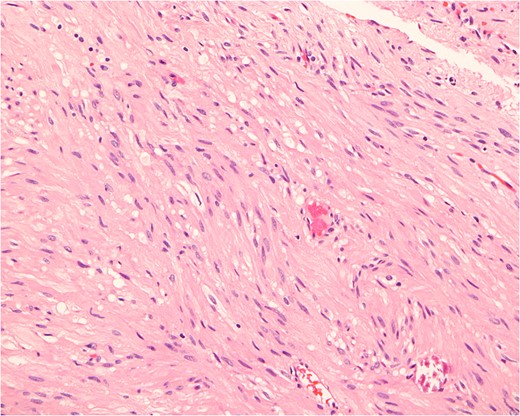

Histopathologically, the tumor consists of cells resembling normal smooth muscle cells. The cells are uniform, elongated and spindle-shaped, and exhibit a cigar-shaped nucleus (hematoxylin & eosin stain, magnification ×200).

Primary cervical leiomyoma with calcification and ossification is extremely rare, with only one case found in the literature [2]. The current case represents a unique tumor in its large size, progression and associated kyphotic deformity. Myofibroma/myofibromatosis could be a differential diagnosis of this patient's pathology. However, the diagnosis of leiomyoma was based on the morphologically apparent smooth muscle differentiation and minimal fibrous tissue element, with strong reactivity of the cells to specific smooth muscle markers, such as desmin and caldesmon [6].